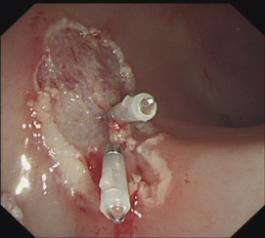

胃底曲張靜脈改良“三明治”注射

3. 食管曲張靜脈硬化劑注射、套扎術(shù)及胃底靜脈曲張組織膠注射栓塞術(shù):在全市首先開展,處領(lǐng)先水平;